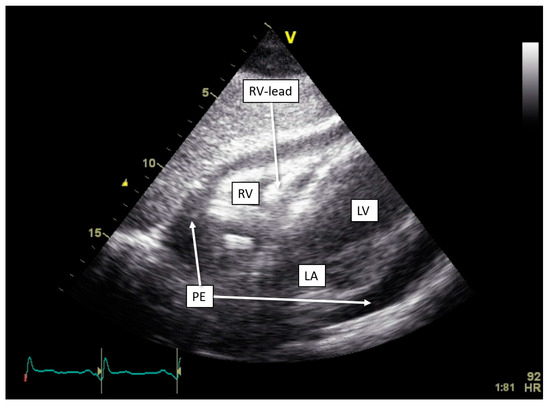

One of our cases, an adult patient with recently repositioned RV and LV lead after spontaneous dislocation of both leads, was admitted with sharp pain upon breathing. Device interrogation detected an OptiVol alarm and non-capture of the RV lead with a programmed output of 2 V. A transthoracic echocardiogram revealed pericardial effusion of 20 mm without signs of tamponade (Figure 4). Both RV lead perforation and reactive pericarditis were considered in the differential diagnosis. Treatment with colchicine and non-steroidal anti-inflammatory drugs resulted in a reduction in the pericardial effusion. Due to a persistently elevated pacing threshold, the RV lead was repositioned, resulting in the normalization of the threshold. Subsequent device interrogation has remained stable ever since.

Figure 4.

Development of pericardial effusion in OptiVol (Medtronic) alert. Transthoracic echocardiogram with subcostal view, showing pericardial effusion measuring approximately 20 mm circumferentially. Abbreviations: LA = left atrium, LV = left ventricle, PE = pericardial effusion, RV = right ventricle.

9.1. Pericardial Disease

The ability of CIEDs to indirectly monitor pericardial conditions, including effusion and lead-related complications, represents a dimension in disease assessment. Our case highlights where thoracic impedance alarm provided early signs of pericardial effusion—specifically in patients with recent lead repositioning—flagging potential pericardial inflammation. However, challenges remain in interpreting thoracic impedance changes, as these readings are meant to detect pulmonary edema and lack high specificity for pericardial pathology alone.